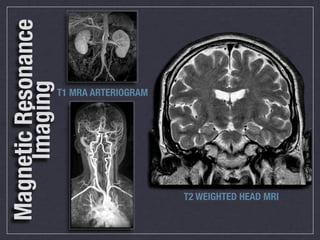

Magnetic Resonance Technologist

Produces images with excellent soft tissue

discrimination using magnetic fields and

radiofrequency pulses to aid in diagnosis

of disease.

MRI is the fastest growing

imaging modality that is

replacing many invasive

procedures in today’s

health care environment

Magnetic Resonance

Imaging

T1 MRA ARTERIOGRAM

T2 WEIGHTED HEAD MRI